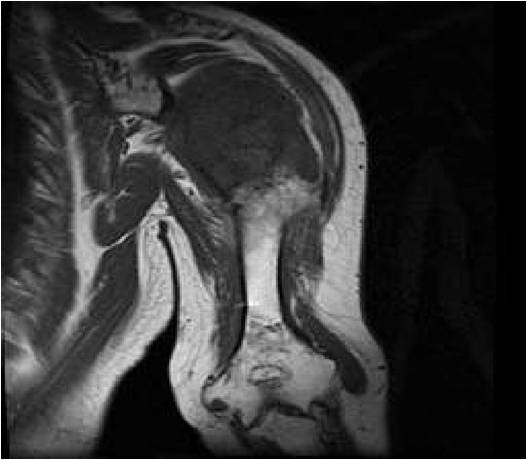

- MRI

- Lobulated margin

- Marked increased intensity long TR images

MRI:

- Lobulated margin (Lobular Growth Pattern)

- T1 Weighted Images: Intermediate Signal Intensity

- T2 Weighted Images: High Signal Intensity

- High water content shows as high signal on T2 weighted images

- There should never be any cortical destruction nor a soft tissue component. If this exists then the tumor must be a chondrosarcoma.

- Endosteal scalloping and cortical expansion is acceptable for phalangeal tumors. In most benign long bone cartilage tumors there is minimal endosteal scalloping but there should be no cortical expansion nor thickening. There should be no cortical destruction and no soft tissue component associated with an enchondroma. Cortical destruction, periosteal thickening, cortical expansion and a soft tissue component indicates a chondrosarcoma of the long bone.